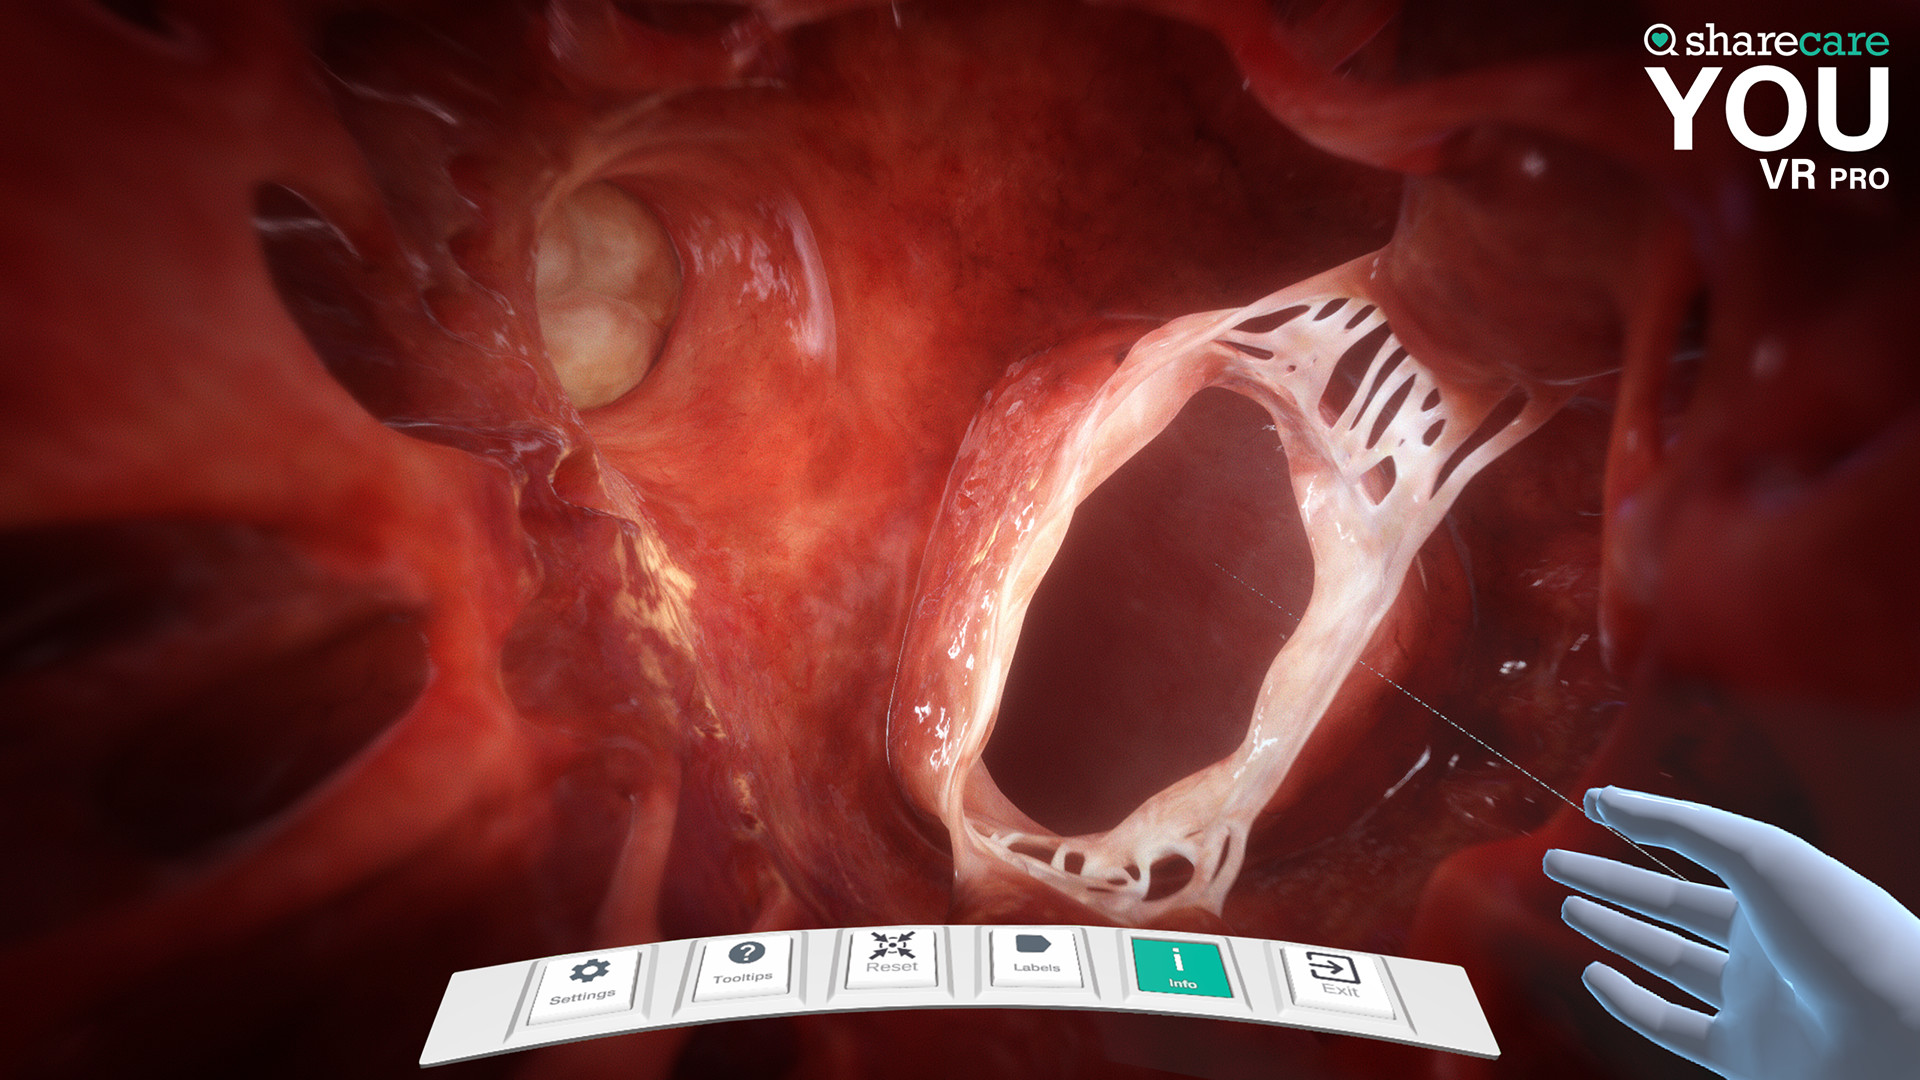

The winner of the 2019 Appy Best VR App is now available on Mac and PC, with more content, bolder graphics, and enhanced features! Sharecare YOU VR is a fully immersive, photorealistic simulation of the human body, enabling anyone to explore its astonishing details in full 360 degrees. Interested in learning about a specific organ? With the click of a button, travel inside, visualize its natural function, and dive deeper. Want to learn even more? Check out the many tags and labels along the way to gain even more information and insight. Easily customize YOU to better understand physiology and simulate disease. You can even personalize our avatars to be a virtual you – your health, your conditions. It really is all about YOU. With YOU VR PRO, users can create visually compelling, high-quality educational content. Build YOU lectures and presentations easily, with the help of video and voiceover recording, and the ability to draw and add your own text. You can also be the star within these videos using our web-cam feature.

- Informative labels and scene information

- Completely updated user interface with unique interactive controls

Sharecare YOU VR PRO includes:

- License to use the software for business, institutional or commercial purposes

Looking to use the content for Business Purposes? Get the Sharecare YOU VR Pro version and have the ability to use all the amazing content for Business Purposes. Take advantage of breathtaking graphics and never seen before views of the human body. Your ability to better communicate human anatomy and physiology with your customers and/or students is at your fingertips!